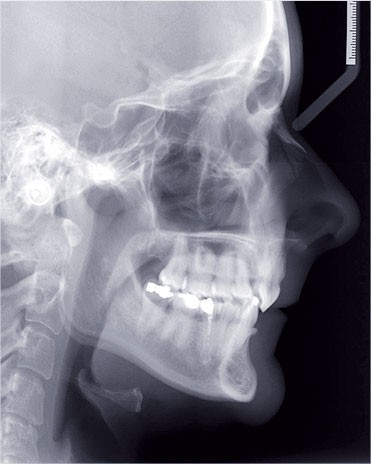

Cas n° 2

Nous lui avons donc proposé un traitement d’alignement avec maintien des 14 et 24 en position de 13 et 23 et optimisation du torque pour favoriser un développement des arcades et chercher à améliorer le sourire et le soutien labial.

La patiente donne son accord pour un appareillage Damon Insignia métal qui permet une individualisation complète des brackets dans les 3 sens de l’espace.